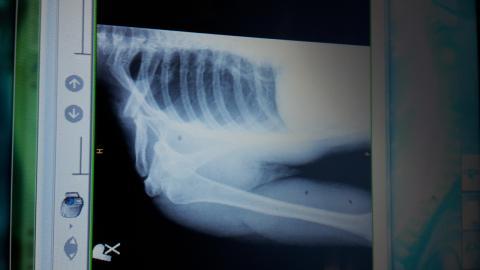

Zlomenina

Pro větší náhled klikněte na obrázek

Zlomenina palkox - 30.6.2015 21:34:06

Dobry vecer,chcel by som sa spytat ci sa da zoperovat zle zrastena zlomenina claviculy? Som uz vyse 2mesiacov po zlomenine a mi to pomerne vadi a k tomu mi trpnu prsty da sa po takej dlhsej dobe operovat znova lamat a drotovat?